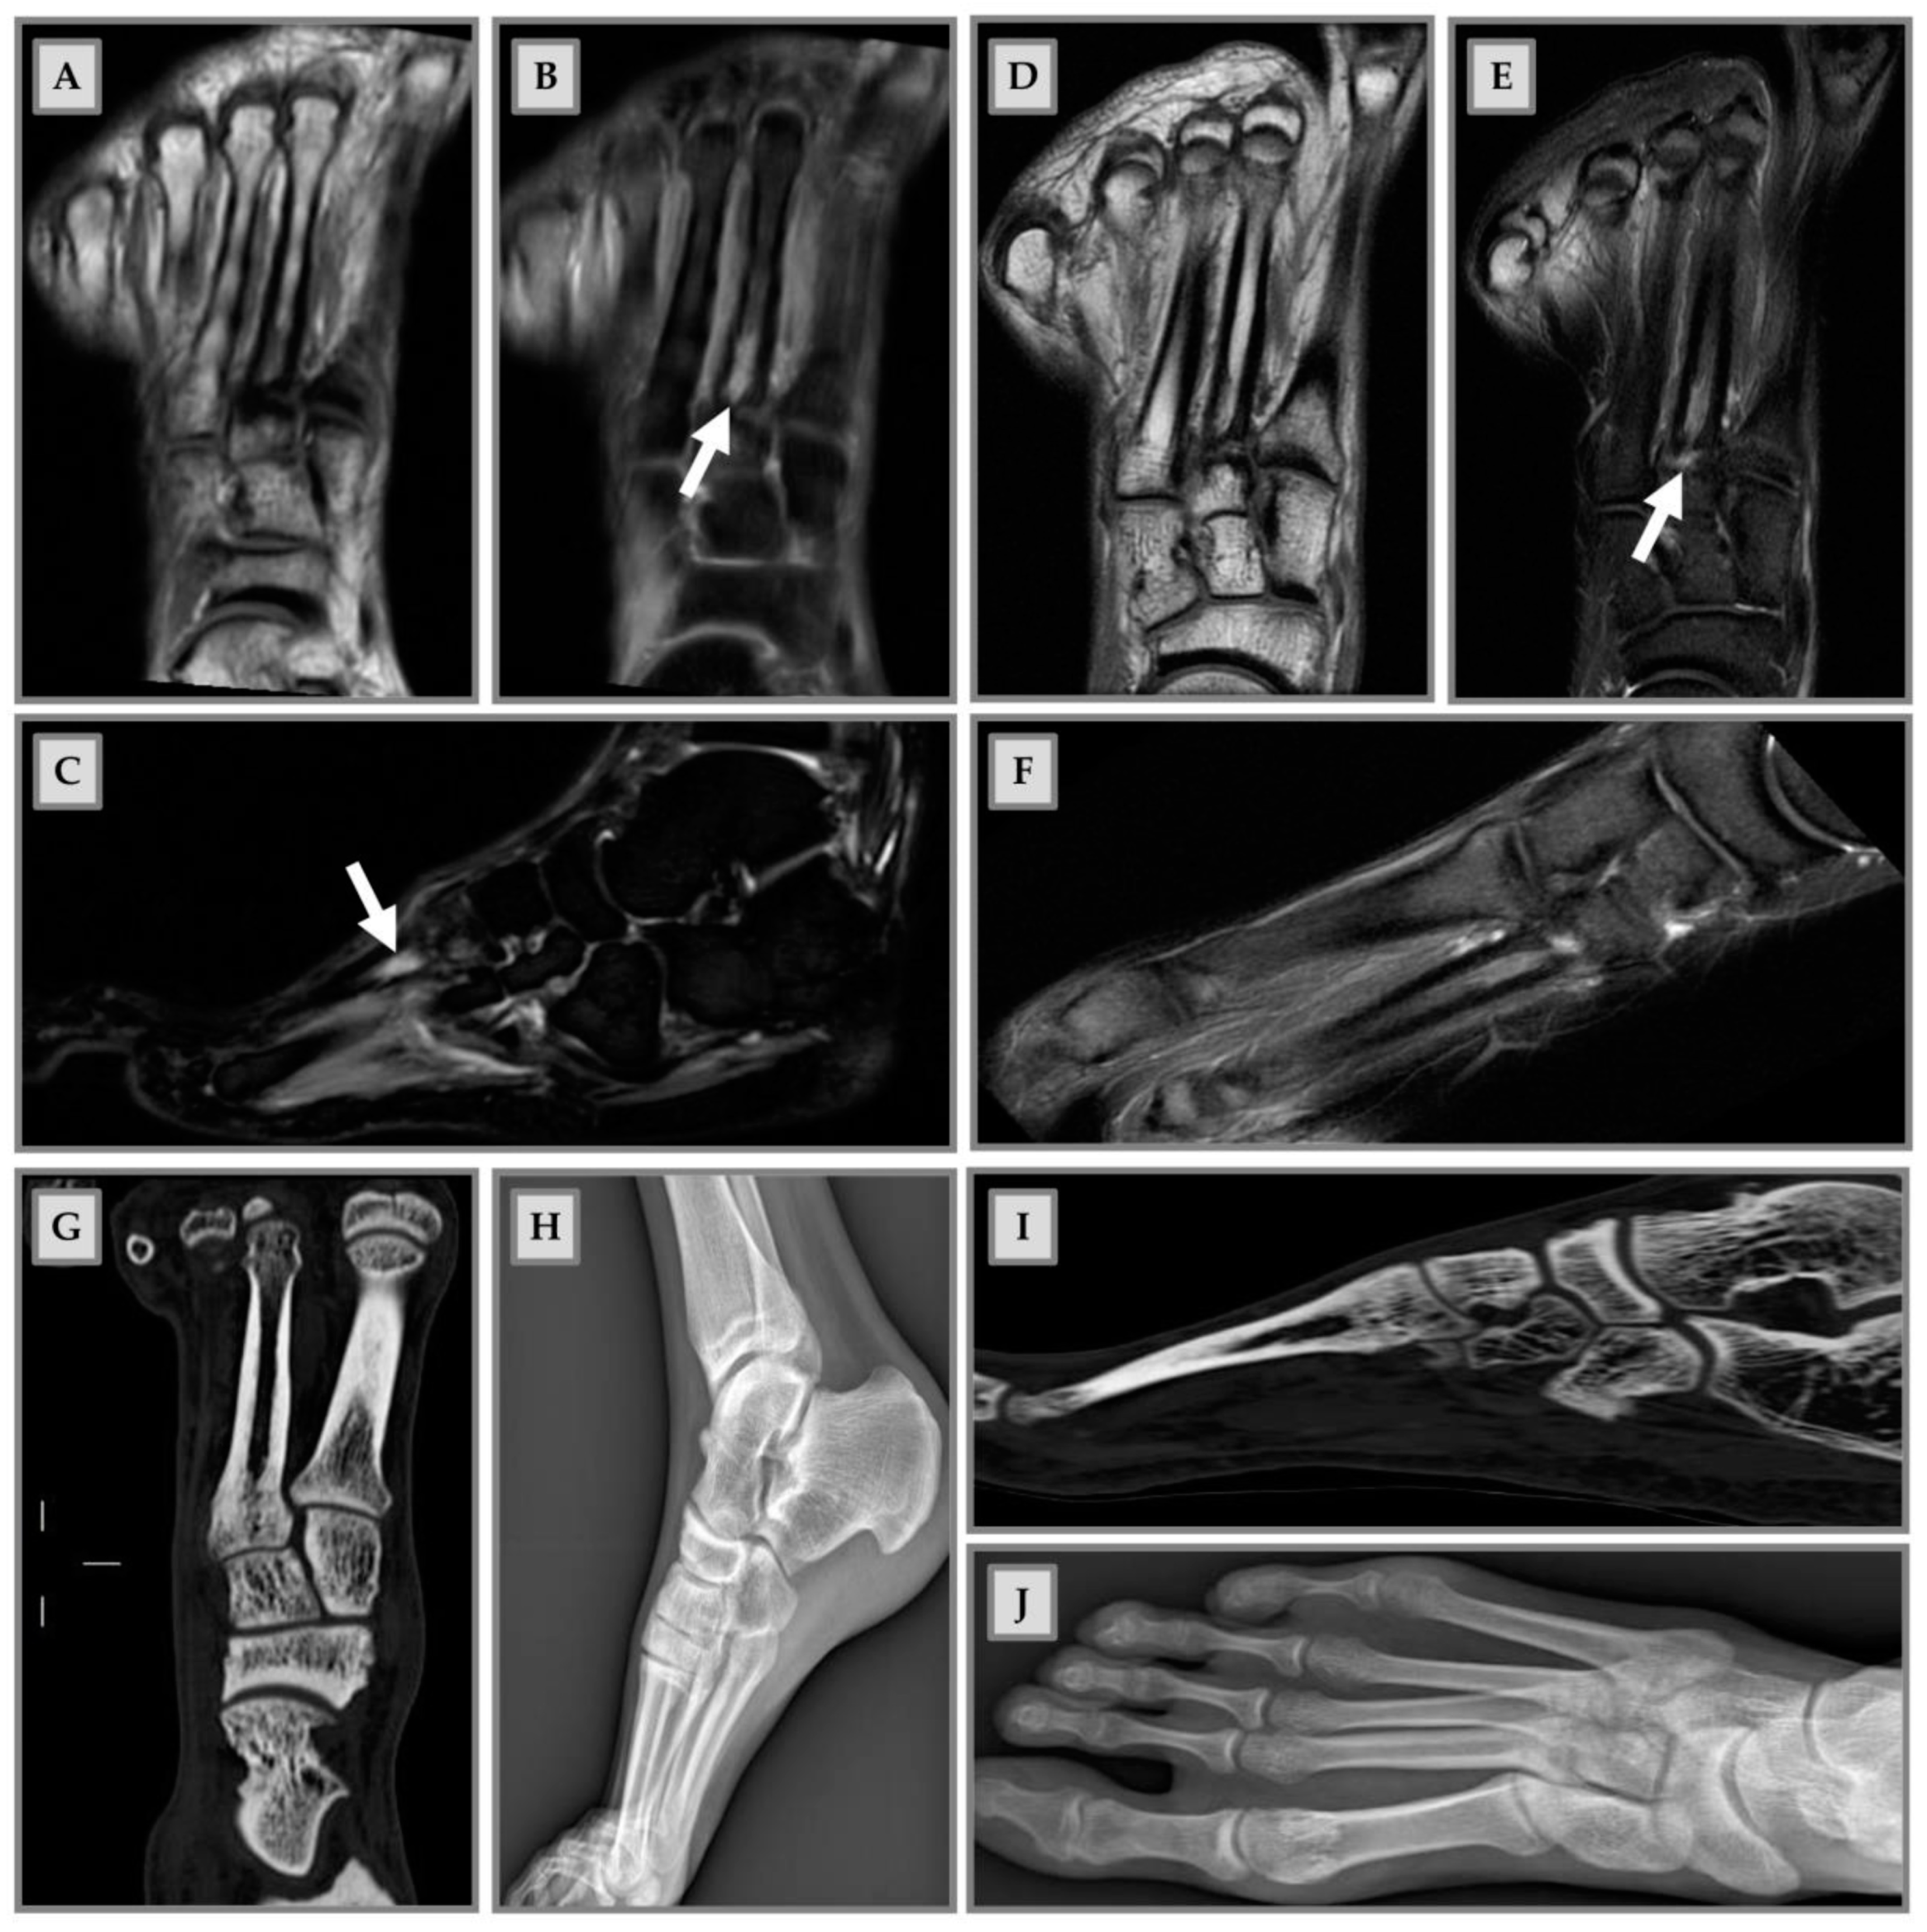

- Kornaat, P.R.; Van De Velde, S.K. Bone Marrow Edema Lesions in the Professional Runner. Am. J. Sports Med. 2014, 42, 1242–1246. [Google Scholar] [CrossRef]

| [21] | 13 men and 3 women | Mean age: 22.9 ± 2.7 | Running | Pubic bones Hips Knee Ankle | Preseason and postseason | MRI | 14 of the 16 athletes had BME lesions before the start of the season: 31/45 were in the ankle joint and foot; 26/45 fluctuated during the season, with new lesions occurring (9/45) and old lesions disappearing (10/45), without causing any symptoms | The observed fluctuation pattern could indicate that BME participate in the normal bone remodeling process and, within 7 months, does not cause symptoms |